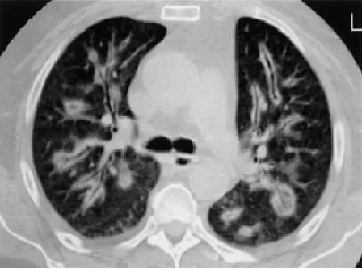

治疗1月后

明确诊断后,主管医师予以相应的治疗方案,程大叔的咳嗽、胸痛症状迅速得到了缓解;1月后复查胸部CT,提示肺部阴影较前明显吸收;程大叔悬着的心,终于放下了。